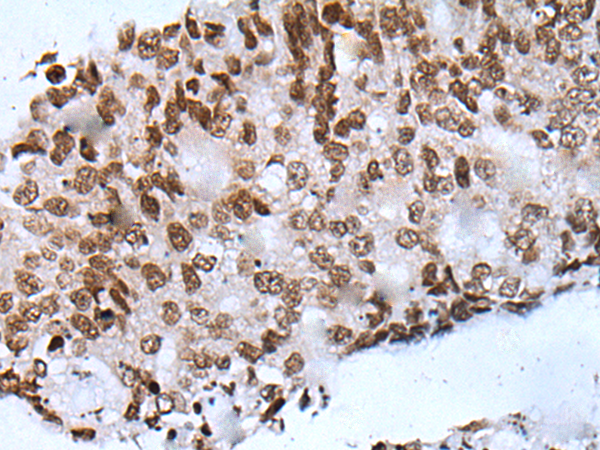

The image is immunohistochemistry of paraffin-embedded Human colorectal cancer tissue using P05988(NHEJ1 Antibody) at dilution 1/20. (Original magnification: ×200) |